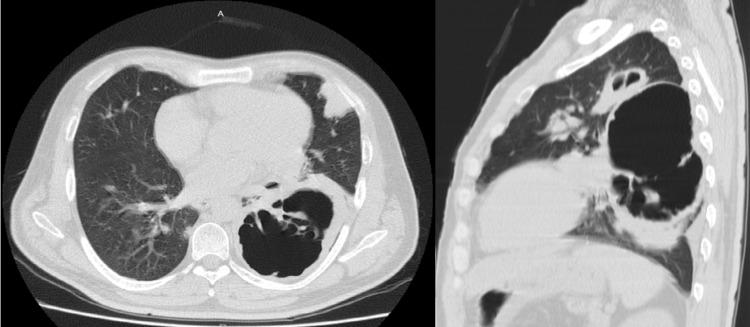

Since the development of antiretroviral therapy (ART) and antibiotic prophylaxis, the incidence of opportunistic infections in human immunodeficiency virus-acquired immunodeficiency syndrome (HIV-AIDS) has been drastically reduced. However, third-world countries remain a fertile ground for medication nonadherence and inappropriate patient follow-up. Here, we present the case of a 42-year-old male with a history of HIV who presented with worsening shortness of breath and atypical chest pain. A chest X-ray and chest computed tomography scan revealed a left parahilar cavitation measuring 86 mm in diameter. A percutaneous lung biopsy revealed . Appropriate antibiotics were started, and the patient's clinical status significantly improved. This case illustrates the devastating consequences of uncontrolled HIV-AIDS. ART and prophylactic antibiotics remain the cornerstone of treatment to ameliorate progressive lung damage in patients.

自从抗逆转录病毒疗法(ART)和抗生素预防措施发展以来,人类免疫缺陷病毒获得性免疫缺陷综合征(HIV-AIDS)中机会性感染的发生率已大幅降低。然而,第三世界国家仍然是药物治疗依从性差和患者随访不当的温床。在此,我们报告一例42岁有HIV病史的男性病例,该患者出现呼吸急促加重和非典型胸痛。胸部X线和胸部计算机断层扫描显示左肺门旁有一个直径86毫米的空洞。经皮肺活检显示……开始使用适当的抗生素后,患者的临床状况显著改善。该病例说明了未控制的HIV-AIDS的毁灭性后果。ART和预防性抗生素仍然是改善患者进行性肺损伤的治疗基石。